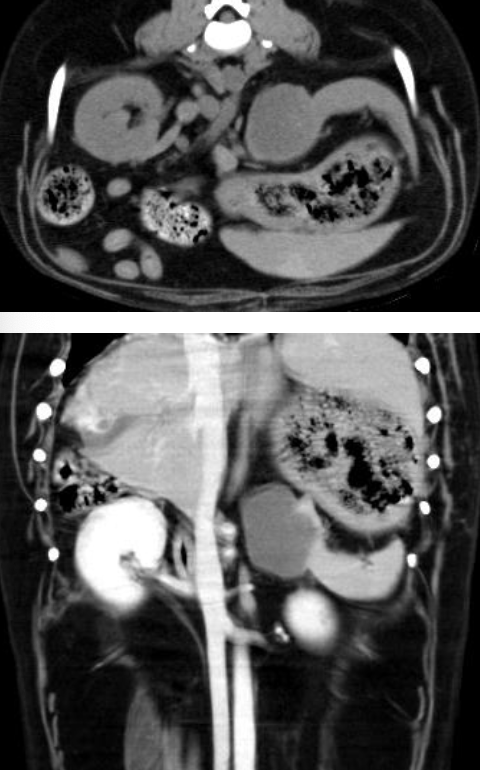

what is the appearance of hemangiosarcoma lesions in the abdomen using abdominal ultrasound?

-heterogenous (hypoechoic to targetoid to mixed)

-cavitation

- +/- peritoneal effusion